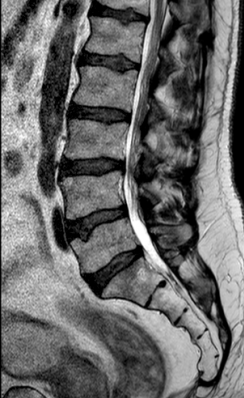

Postoperatorio

Los cambios postoperatorios son muy sutiles en la RM. Quizá en una RM dinámica (en bipedestación y extensión) pudieran apreciarse mejor.